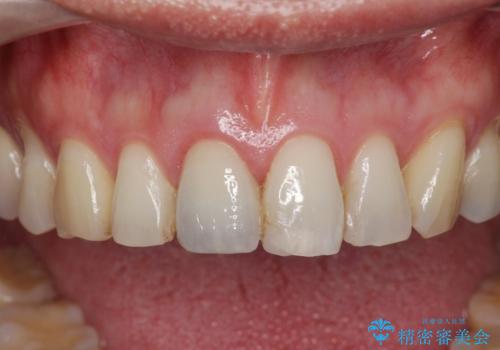

周囲の歯の色調に合わせた、自然なセラミック治療を行うことができましt。